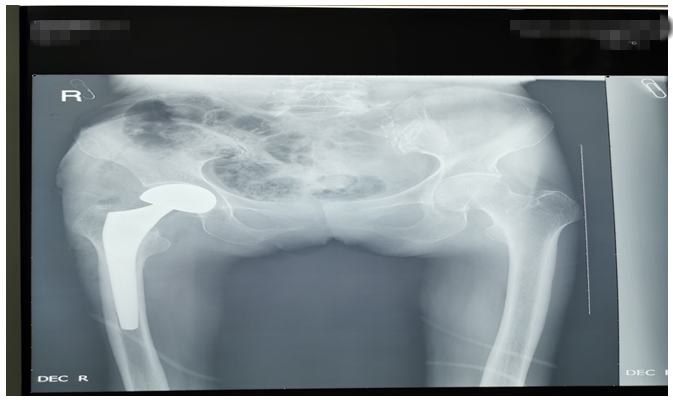

還有一位76歲鄧大媽,外傷致右側股骨頸骨折。外傷后因疫情鄧大媽一直未就診,在家非常痛苦,因疼痛不能平臥,一直坐位,臀部褥瘡形成,同時被骨折疼痛折磨地夜不能睡、不思飲食。鄧大媽基礎病較多,有高血壓病、腦梗塞、心臟病等病史,因骨折后時間長、錯位明顯,入院后積極治療內科疾病,完善各項輔助檢查,在麻醉師及內科醫(yī)師協(xié)助下,為鄧大媽成功行右側髖置換術,手術順利。術后鄧大媽的臉上又有了笑容,夜間也能休息好了,術后第二天就開始下床活動,家屬看到自己的老母親恢復地這么好,非常滿意。(見下圖)

右髖正側位手術前后對比圖